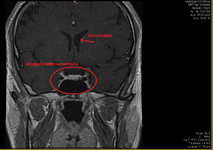

Weil ich Angst habe das mein Hirn von Schwermetalle geschädigt ist, und die Radiologie es nicht sieht ( weil die Microweiße Punkte im Hirn keiner Bedeutung zuweisen, diese sich aber über kurz oder Lang vergrößern können) habe ich die CD's der beiden MRT's aus den letzten beiden Jahren angefordert und möchte mittels Daunderers Bildmaterial mein Hirn mal vergleichen. Vielleicht erkenne ich ja Auffälligkeiten.